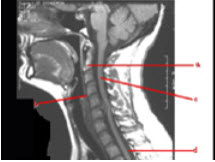

39、填空题

如图为脊髓失状面MRI T1加权像请标出a___________b___________c_____________d______________。